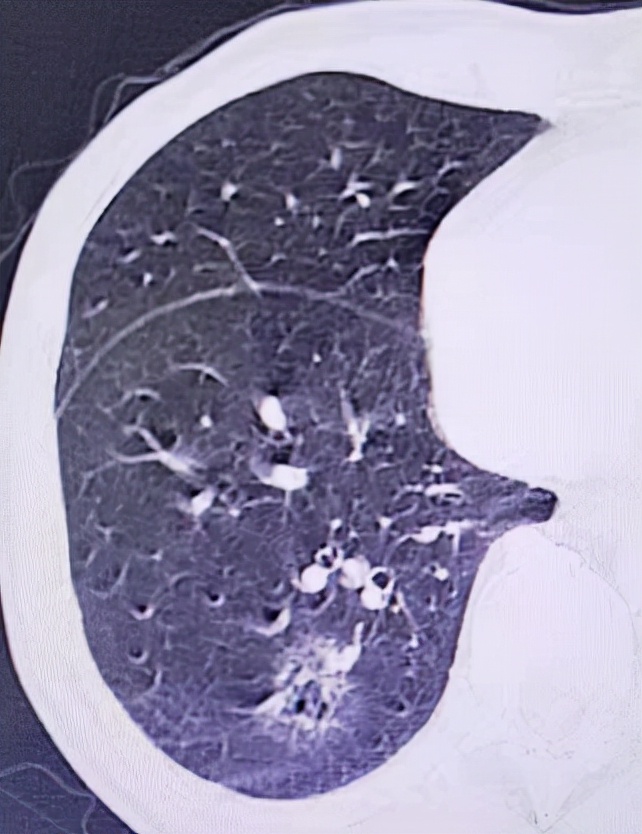

术后10天CT复查清晰可见冷冻肺毁损范围,胸腔出现反应性积液。

术后半年复查肺毁损及反应性积液吸收,可见瘢痕残留。